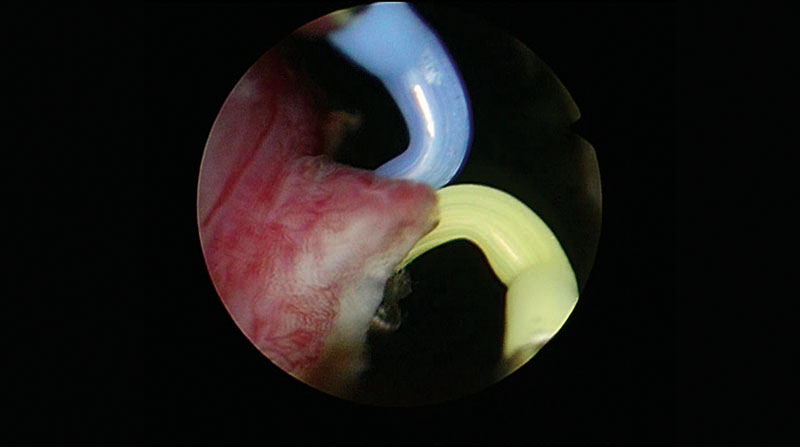

03|Vaporization of the Medial Lobe, of Basal Portions of Lateral Lobes, and of the Floor of the Prostatic Cavity

Vaporization of medial lobe and proximal part of the side lobes until the 5 o’clock and 7 o’clock position.

Vaporization is done in layers instead of deep grooves.